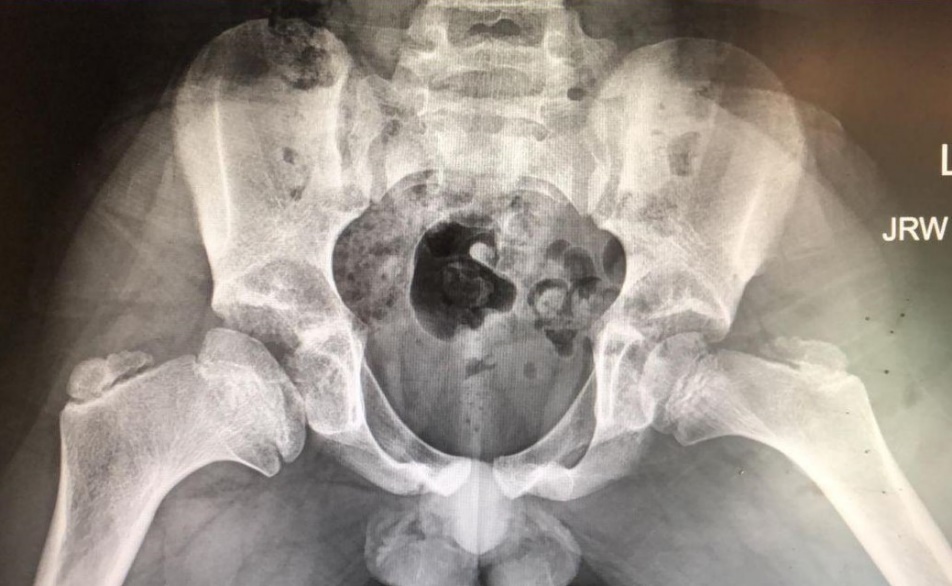

Central Head Reduction Osteotomy

This is a powerful technique to make a large round head smaller, flat head rounder, and remove unhealthy cartilage from central parts of the head. It requires experience with surgical dislocation, extended retinacular flap development, and creativity to design the bone cuts to match the two halves after excising some of the central part of the head. Preop templating helps, but intraoperative versatility is required to get the best results.

• Hinged abducted from a large head not fitting the acetabulum

• Central part of the head removed

• The smaller head fit the socket well after head reduction osteotomy